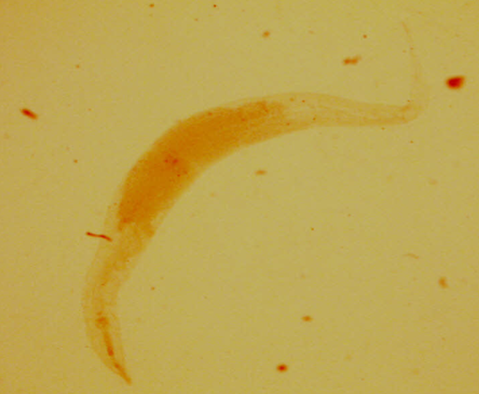

Ancylostoma duodenale - Tęgoryjec dwunastnicy - Osobnik dojrzały